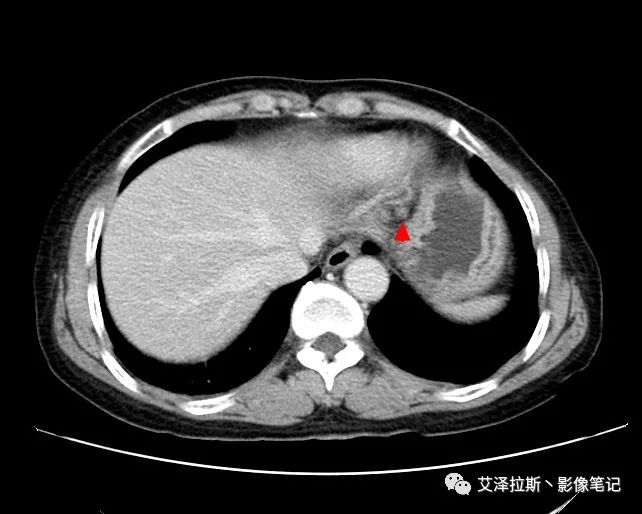

圖1 平掃+增強(qiáng)各期

圖2 腫瘤

【影像所見】 胃竇部狹窄,胃壁環(huán)形增厚,小彎側(cè)見一巨大潰瘍,周圍伴“環(huán)堤征”,漿膜面不完整,胃周脂肪見網(wǎng)格狀條索影,病灶與肝臟左葉、胰腺鉤突脂肪間隙消失,增強(qiáng)掃描病灶明顯強(qiáng)化。引流區(qū)內(nèi)約15個區(qū)域淋巴結(jié)受累。

【診斷意見】 胃竇部胃癌(T4N3期) 該病例腫塊突破漿膜層,與肝臟左葉、胰腺鉤突分界不清,脂肪界面消失,定為T4期; 受累及的淋巴結(jié)為15個區(qū)域,定為N3; 有無遠(yuǎn)處轉(zhuǎn)移尚不明確,所以M期暫時無法確定。